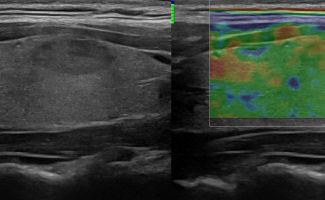

Με την τριπλή μελέτη του Θυρεοειδούς Αδένα, που περιλαμβάνει το B-Μode, το Έγχρωμο Υπερηχογράφημα και την Ελαστογραφία, γίνεται μια ολοκληρωμένη χαρτογράφηση του θυρεοειδούς αδένα. Το περίγραμμα, η αγγείωση και η ελαστικότητα του αδένα, καθώς και η υφή μίας πιθανής βλάβης αξιολογούνται με ακρίβεια και αξιοπιστία.

• Εστιακές αλλοιώσεις (όζοι του θυρεοειδούς αδένα)

• Κακοήθεις βλάβες (καρκίνος θυρεοειδούς)